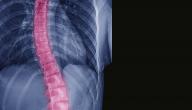

العمود الفقريّ

العمود الفقريّم يجمع بداخله عدد كبير من الأعصاب الواصلة بين الدماغ والتي تتفرع لباقي أجزاء الجسم بعد ذلك وتجتمع هذه الأعصاب داخل هذا العمود مرورا بما يُعرف بقناة العمود الفقريّ، ويوجد 31 زوج من أعصاب العمود الفقريّ، وتشكّل أعصاب العمود الفقريّ والدماغ الجهاز العصبيّ المركزيّ، وتعمل الأعصاب على إيصال المعلومات الصادررة عن الدماغ لباقي أجزاء الجسم، ويُغّلف الدماغ بثلاث طبقات من الأنسجة الضامة، ويملأ الفراغ بين الطبقة الخرجية والوسطة سائل يُعرف باسم السائل النخاعي وهو سائل عديم اللون يقاوم الصدمات التي يتعرض لها الرأس بحيث يعزل الدماغ عن عظام الجمجمة ويمنع اصطدام الدماغ بالعظام مما يقلل من خطر وقوع ضرر بالدماغ.[١]